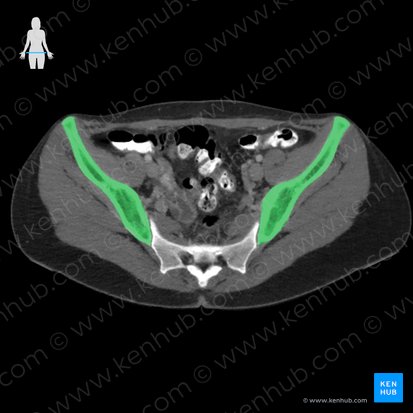

O ílio, também chamado de osso ilíaco, é o maior e mais superior dos três componentes da bacia.

Ele tem uma porção inferior menor, que contribui para a formação do acetábulo, e uma porção maior superior (ou asa) que se estende em forma de leque e fornece apoio ao abdome inferior (ou pelve falsa).

Os outros dois componentes da bacia são o ísquio, que forma sua porção posterior e inferior, e o púbis (ou osso púbico), que se localiza anteriormente. Os três componentes da bacia se unem no acetábulo.